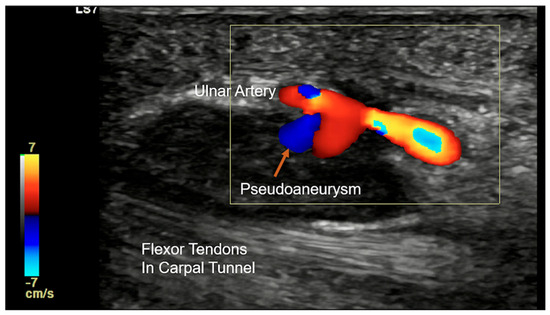

Guyon’s canal can be affected by post-operative scar, rheumatoid arthritis causing pannus formation, or trauma-related lesions. Traumatic injuries in Guyon’s canal include both sharp and blunt trauma. Sharp injury is not uncommon and can result in Ulnar nerve transection and arterial injury. Depending upon the extent, the nerve may be partially or completely lacerated. Complete laceration can lead to the formation of stump neuroma, which appears to be a bulbous enlargement of the stump of the lacerated nerve (Figure 17). Blunt injury can involve bone as well as soft-tissue structures [24]. Hook of hamate fracture can occur as a result of a fall or in sports injury from racquets or bats while swinging. If occult on the standard radiograph, a carpal tunnel view will be able to demonstrate the fracture. CT and MRI can be considered if the radiograph is negative and there is a high suspicion of injury. Repeated trauma in this region in persons using a hammer/vibrating tool and in athletes is also seen (see Section 4.2). Repetitive trauma to the ulnar artery against the hook of the hamate can cause the formation of an aneurysm/pseudo-aneurysm or thrombosis (Figure 18) [25].

Colour Doppler longitudinal ultrasound image showing ulnar arterial pseudoaneurysm (orange arrow) in a case of hypothenar hammer syndrome.